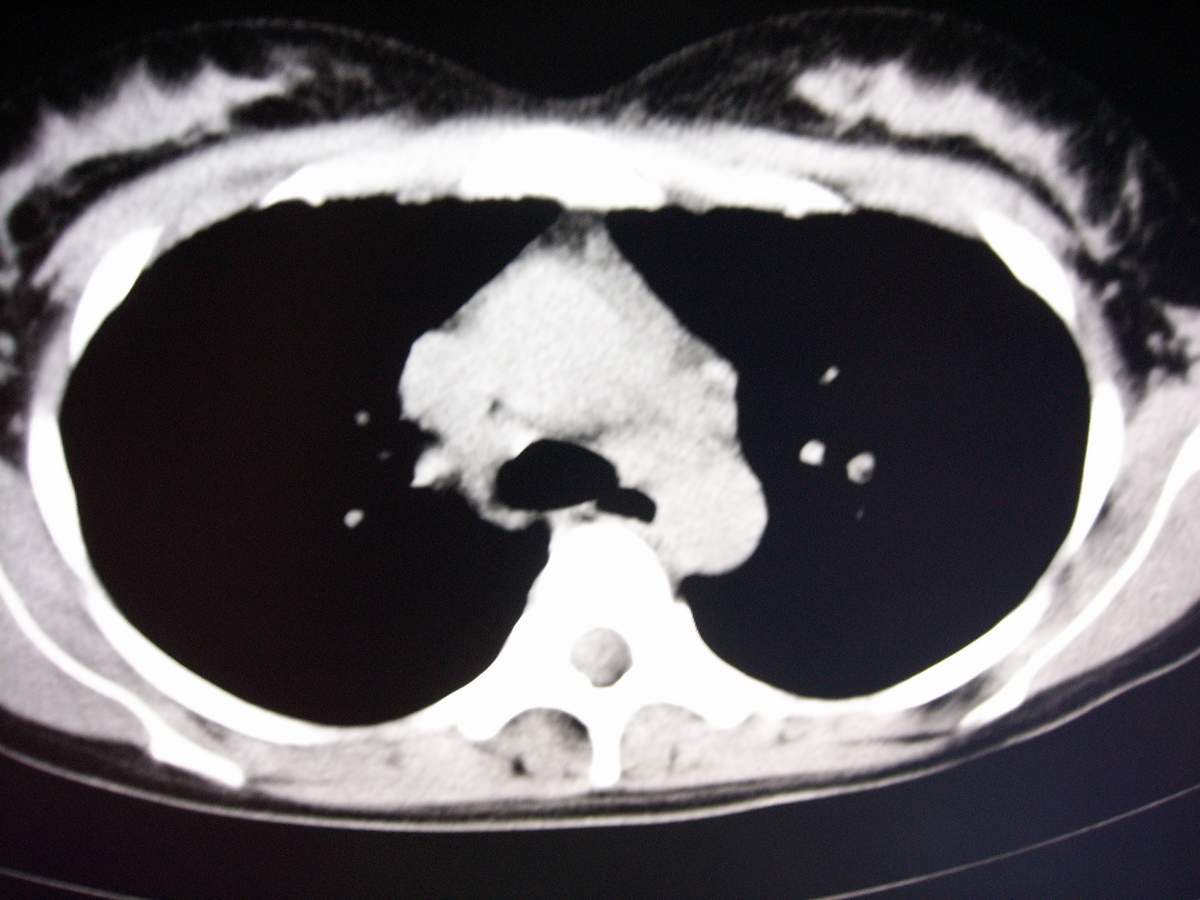

标题: CT7371:[讨论]肺部病变!

女,咳嗽、气喘2月余。

双肺弥漫性病变, 冠状重建肺血管增粗,建议继续上传详细临床资料,x线片

双肺弥漫磨玻璃样影,边界不清,似蝶翼征。肺纹理增多。

考虑:肺泡蛋白沉积症。建议临床进一步检查。